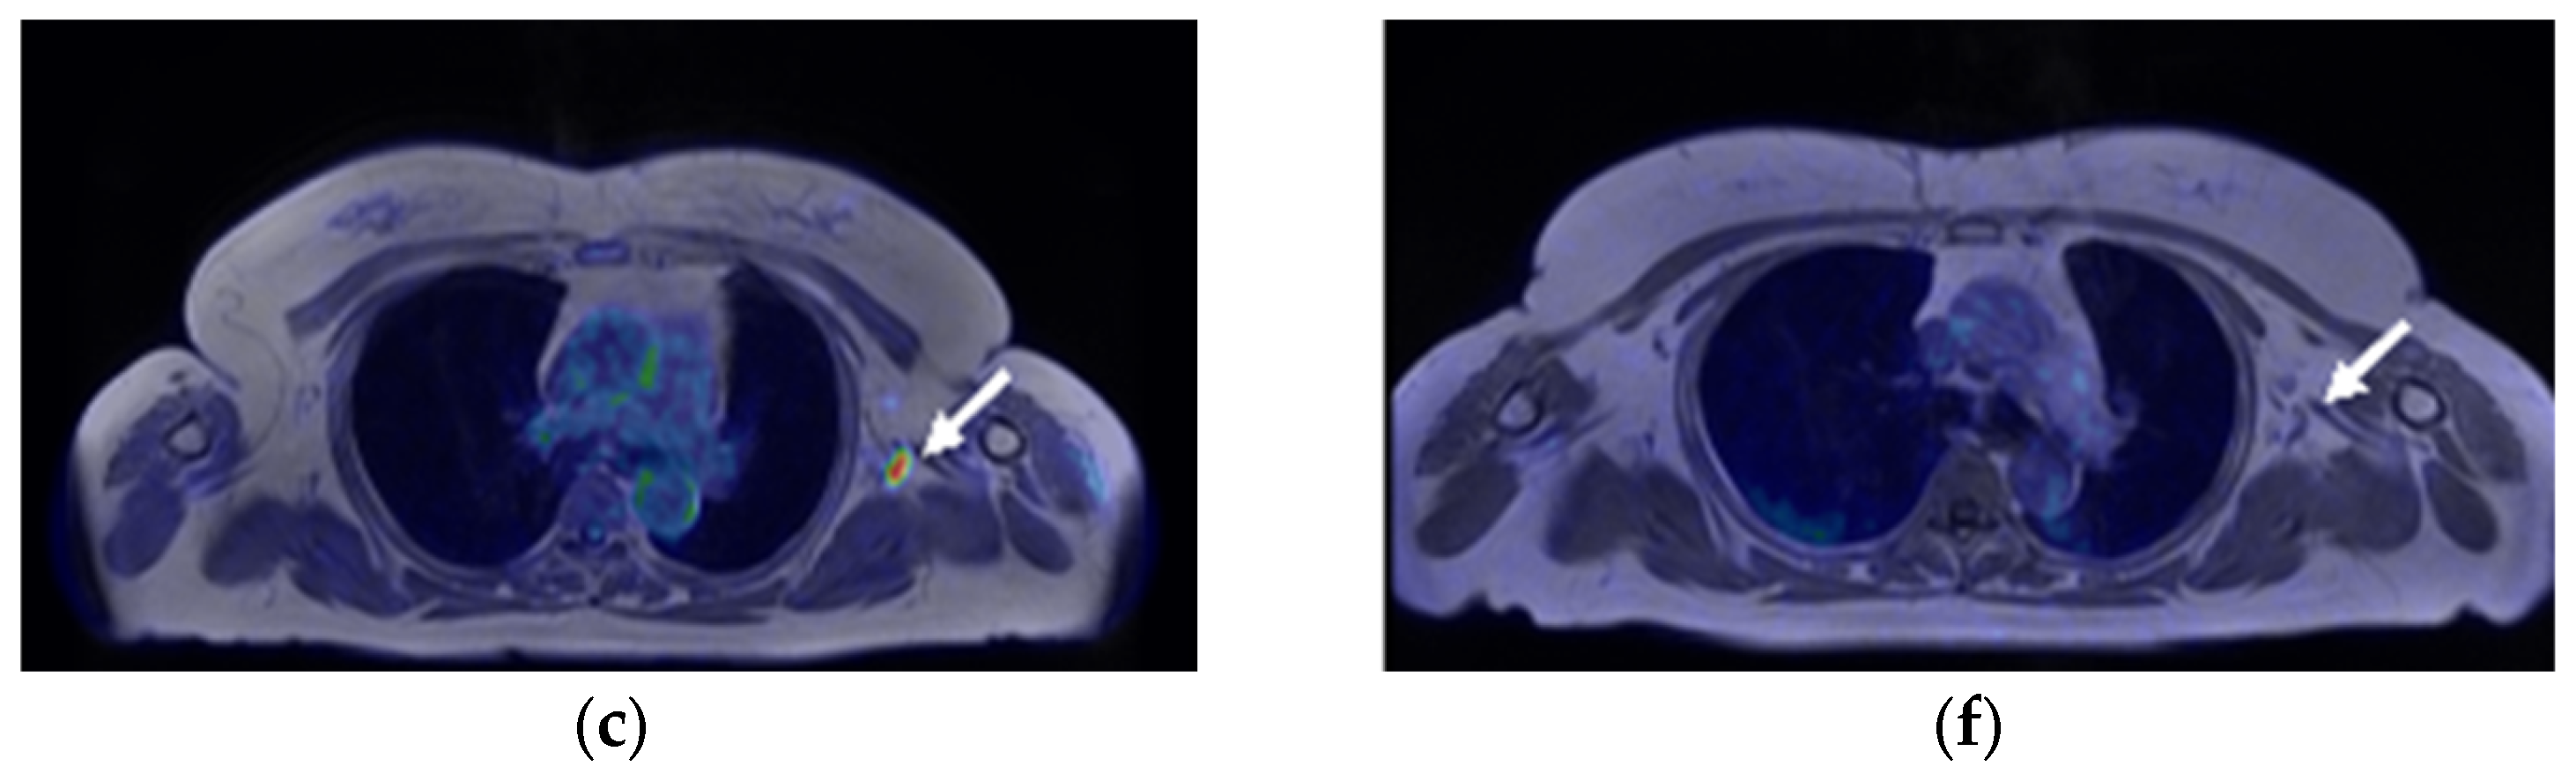

A 59-year-old woman was diagnosed with ER-positive left breast cancer on histopathological examination, including hematoxylin and eosin (H&E) staining and immunohistochemistry (IHC) (ER 90%, PgR 30%, HER2 score1, MIB-1 index 30%) She underwent [18F]FDG PET/magnetic resonance imaging (MRI) for preoperative staging. The primary lesion in the breast, as well as multiple level I and II left axillary lymph nodes, showed significant FDG uptake (Figure 1a and Figure 2a–c). The patient had received the COVID-19 vaccine in the upper left arm 3 days prior to examination, and there was marginal FDG accumulation in the left deltoid muscle, suggesting inflammatory changes due to vaccine administration. Nineteen days after [18F]FDG PET/MRI, [18F]FES PET/MRI was performed again to assess ER expression in the lymph nodes (Figure 1b and Figure 2d,e). The largest axillary lymph node showed considerable FES uptake (Figure 1b and Figure 2d, red arrow), a finding consistent with lymph node metastasis; however, the other nodes with FDG accumulation did not show remarkable FES uptake (Figure 1b and Figure 2e,f, white arrows), indicating that the FDG uptake was due to inflammatory changes associated with vaccine administration. Uterine leiomyoma, another estrogen-dependent tumor, showed intense [18F]FES uptake in the pelvis (Figure 1b, yellow arrowhead).

Figure 2.

(a–c) [18F]FDG axial PET/magnetic-resonance (MR)-fused images and (d–f) [18F]FES PET/MR-fused images of left breast cancer and multiple ipsilateral axillary lymph nodes. The left breast cancer shows significant uptake on both ((a), arrowhead) [18F]FDG and ((d), arrowhead) [18F]FES PET. ((a–c), arrows) The multiple ipsilateral axillary lymph nodes show intense [18F]FDG uptake. ((d), red arrow) The largest ipsilateral axillary lymph node in level I shows intense [18F]FES uptake, whereas ((e,f), white arrows) the other nodes do not show significant uptake.

The patient underwent left mastectomy and left axillary lymph node dissection. Histopathological diagnosis of the excised specimen of the left breast lesion via H&E staining led us to diagnose the lesion as invasive ductal carcinoma with intraductal extension (pT2, Figure 3a). Of the 20 dissected left axillary lymph nodes, only the largest excised lymph node specimen was diagnosed as lymph node metastasis via H&E staining (Figure 3b). The patient underwent postoperative chemotherapy and has not relapsed thus far.